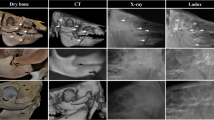

CT was undertaken for limbs post shooting. With the availability of the scanner being limited to out-of-hours periods due to clinical use, limbs were frozen immediately after shooting until 72 hours prior to the scan date when they were then defrosted. The scanner used was a dual source (2 × 64 slice) Siemens SOMATOM Definition MSCT scanner (System SOMATOM Definition AS, 64622, Siemens AG, Wittelsbacherplatz, DE – 80333 Munchen, Germany). Scans using a standard adult pelvis protocol (exposure figures were 120 kV and 25–32 mAs) with 1.0-mm slice soft tissue and bony reconstructions in the axial, sagittal, and coronal planes. The limbs were wrapped in Clingfilm and scanned initially in situ without contrast. For each limb, a small hole was then made in the Clingfilm over the entrance wound and 10–20 mls Omnipaque 300 contrast (OMNI300, GE Healthcare) was subsequently injected whilst simultaneously probing the wound track via a 5-in. mixing tube connected to a 50-ml Omnifix Luer Lock Solo syringe. The volume range was because contrast was injected via the entrance wound until it could be seen starting to ooze out of the exit wound, then injection stopped with no further contrast added. The entry hole in the Clingfilm was then sealed with duct tape to prevent leakage of the contrast, and the limb re-scanned. The images were reviewed and reconstructed as multiplanar (MPR) and 3D reformats within AGFA Enterprise Imaging Patient Archive and Communications System (PACS) and as part of the Syngo CT2012B software package provided with the CT workstation [48].

Computed-tomography

Limbs undergoing CT produced a series of comprehensive images as exampled in Figs. 9, 10, and 11. The limbs were imaged axially and then MPR and 3D reformats were produced from these images. The presence of contrast allowed precise delineation of the GSW track in multiple planes of view. This, alongside the measurement tools within the software package used to view the images, allowed dimensional measurement of the complete GSW tracks from each limb scanned, which are displayed as mean with standard deviation (SD) and coefficient of variation (CV) for each measurement (Table 2). Wound patterns from projectiles were observed to enter from the lateral thigh surface, traverse the posterior muscle compartment of the thigh (hamstring muscles) whilst crossing an intermuscular plane around the mid-way point, before exiting via the medial thigh surface.

3D reconstructed images, arrows indicate projectile direction of travel, white dotted circle indicates entrance wound, black dotted circle indicates exit wound—clockwise from top left: front face of deer limb without digital subtraction, rear face without digital subtraction, right limb wound profile, left limb wound profile

Contrast medium successfully penetrated each complete wound track to allow visualisation on CT images. CVs for NL, H1, and D1 are relatively large as would be expected due to the variability seen within GSW patterns even under controlled circumstances.

Computed-tomography

CT of limbs following direct percutaneous injection of contrast and MPR gave demonstrable results with precise mapping of the GSW track within the samples scanned. Specific aspects of the wound patterns that were measured (as shown in Table 2) are comparable to data collected within other studies examining GSW patterns [5, 8, 10, 12, 49]. Whilst the application of CT for GSW within forensic fields is already proven [45,46,47], by collecting precise dimensional GSW pattern data using the method outlined in this study, contrast CT scanning offers a further tool for data capture to the ballistic researcher, particularly within otherwise opaque materials under study, e.g. animal or human tissues as opposed to gelatine. Despite these advantages, a significant disadvantage was the availability of appropriately trained personnel and limited access to the scanner itself due to pressures of clinical use. This could have potentially caused difficulty with a narrow timeline for data collection, though in this study was not an issue. Whilst no significant cost was incurred for this study due to the affiliations of authors with the institute utilised, other researchers may not be able to benefit from such an arrangement. The software for image reconstruction was also complex and required a user not only trained in its use, but also proficient with it in order to facilitate image analysis. Contrast penetration of the true wounding pattern was assumed, though it would be possible for elements of the wound profile and the distorted anatomy to prevent complete contrast penetration to all areas. This must be considered upon reviewing the images collected.